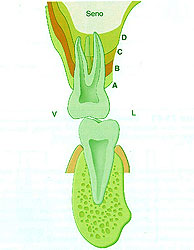

REF: SEGUNDA ENTREGA DEL CURSO: ANATOMÍA OCLUSAL INDIVIDUAL — ABBUTMENTS ANGULADOS POR IMPLANTES INCLINADOS Las piezas dentarias presentan un diseño biomecánico que a partir de su perpendicularidad a la Espiral Dinámica (Willams Mc Horris .Visión tridimensional de la Curva de Spee y de la Curva de Wilson.) reciben las fuerzas de manera axial al hueso receptor. Aplicando técnicas de análisis tridimensionales de elementos finitos y métodos fotoelásticos se ha podido comprobar que cuando se aplican cargas anguladas se producen grandes tensiones a nivel de la cresta ósea.(Misch). (Tomado de Misch) Con una angulación entre 0º y 15 º del abuttment la concentración de tensiones en la zona de la cresta es similar. — ALTURA DE LA CORONA Otro concepto importante es la Relación Corono – Implantaria. Sabemos que debido a la pérdida en altura del hueso es frecuente observar que el largo coronario supera el largo de la implantación endo ósea, situación que es según Misch, mas comprometida en importancia a la de la angulación del abbutmentt , provocando mayores reabsorciones crestales en el caso de recibir fuerzas no axiales. De la misma manera que en la oclusión dentaria, esta situación es manejable en Implantología actuando de manera axial sobre la pieza implantada o dentaria para que las fuerzas recaigan sobre el eje implantario o dentario. En ese sentido es importantísima la situación de los Contactos Interoclusales de manera Tripódica para mantener la Axialidad y sobre todo la Estabilidad de la Oclusión supra Implantes. Misch encuentra útil utilizar coronas de baja Altura Cuspídea incrementando el surco central dos o tres milímetros, con lo cual desde mi punto de vista no solo se disminuye la Eficacia Masticatoria, sino que se acerca al concepto de Céntrica Larga lo que a mi juicio incrementa el juego muscular e induce al Bruxismo.- En cuanto al contorno coronario, debido a que la mayoría de los Implantes tienen una plataforma menor en su emergencia que la que presentan la piezas naturales, es lógico reducir dichos contornos para evitar atrapamiento de alimentos y lograr una correcta fisioterapia natural de la encía peri implantaria. Es por eso la “Premolarización “ un recurso adecuado ya que recordemos que un premolar contiene en su estructura Oclusal la mitad de los componentes anatómicos de un molar los que aún así, cumplen con los conceptos de una OCLUSIÓN ORGANIZADA. REF: SEGUNDA ENTREGA DEL CURSO: ANATOMÍA OCLUSAL INDIVIDUAL Lo importante es que la plataforma del Implante se encuentre debajo de la resultante de las fuerzas axiales. Como dijimos es fundamental relacionar la anchura coronaria con el diámetro de la plataforma del Implante.(Misch). Crestas Estrechas Crestas Estrechas Premolarización Sin embargo si se tiene en consideración el Área Funcional Oclusal (de punto de contacto A a punto de contacto C (45% de su ancho total coronario), observaremos que la reducción coronaria en sentido vestibulo lingual o palatino, no altera la Eficacia Masticatoria ya que las áreas coronarias periféricas a la zona funcional solo sirven para conducir el alimento hacia la inserción del Implante produciendo el masaje fisiológico del alimento , y como la superficie de emergencia es menor que en un diente, lo que se conserva es la parte auténticamente necesaria y funcional de la cara oclusal. Funcionalidad Molar en el Plano Frontal REF: SEGUNDA ENTREGA DEL CURSO: ANATOMÍA OCLUSAL DE CONJUNTO EN EL PLANO FRONTAL Para obtener Axialidad en hueso Div. A es preciso conservar perpendicularidad entre el Implante y la Fosa Central de la Corona, pero a mi juicio, eso solo debe tener una recepción de la carga mediante puntos de contacto equilibrados preferentemente Tripódicos, ya que es el Tripodismo el esquema mecánico básico de estabilidad en la Física Mecánica. En el hueso Div . B –C y D ese eje debe lingualizarse dado el sentido de la reabsorción que se produce. (Tomado de Misch) Oclusion implanto asistida 1ª parteBinderman en un estudio de elementos finitos realizado en la década del 70, concluyó que todos los diseños de Implantes estudiados soportaban menor tensión si la carga era axial al eje mayor del Implante.